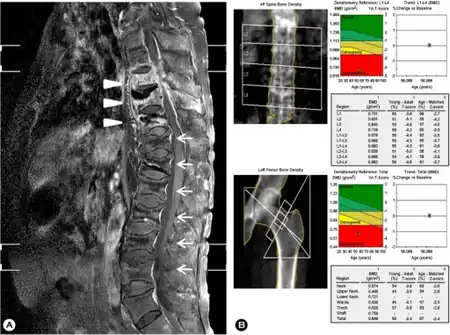

a) MRI of spine - spondylitis of T8, 9, 10 and subligamentous abscesses arrow b) Low bone mineral density at lumbar spine/femur